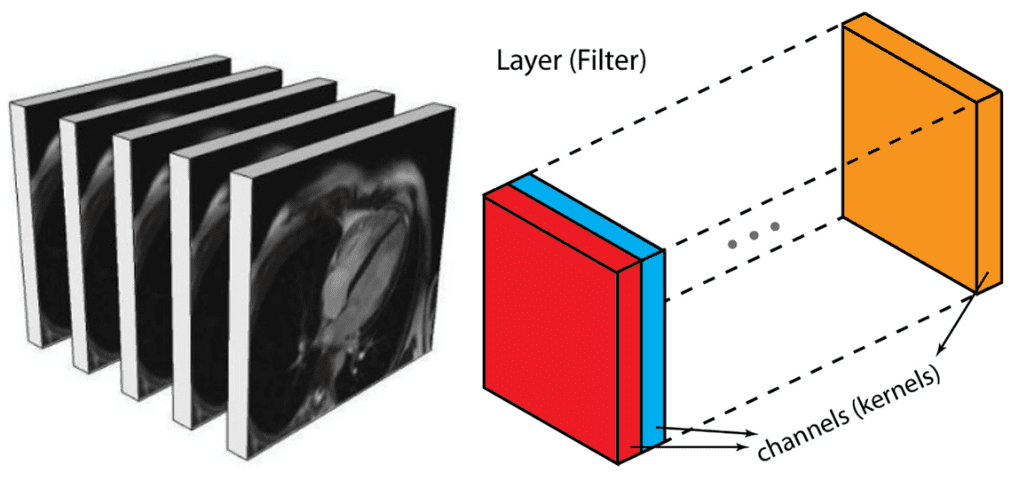

或者,您可以将它们表示为类似于中间层的输出。在深度架构中,我们通常有多个特征图,这实际上是一个 3D 张量。如果有理由相信附加维度之间存在模式,则执行 3D 滑动卷积是最佳选择。医学图像就是这种情况。与编码 2D 域中对象的空间关系的 2D 卷积类似,3D 卷积可以描述 3D 空间中对象的空间关系。由于2D 表示对于医学图像来说是次优的,我们将在这篇文章中选择不使用 3D 卷积网络。

医学图像切片可以看作是一个中间层的多个特征图,不同的是它们之间有很强的空间关系